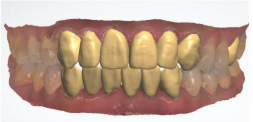

修复前的牙齿

修复后的牙齿